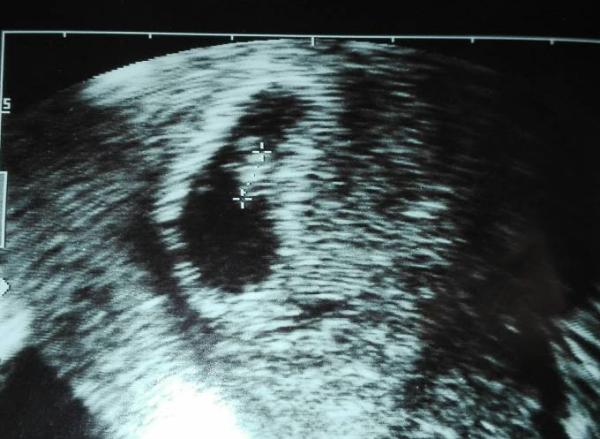

Hallo meine lieben ich bin gerade geschockt. ich war beim Frauenarzt und hab wieder ein Ultraschall Bild bekommen. ich hatte meine letzte Periode am 18. November. rechnerisch wäre ich somit in der 8ten Woche. war am 05 01 beim fa wo ich das erste Bild bekam dieser meinte es sehe nach 5te Woche aus heute war ich bei der Vertretung und dieser sagte mir knallhart die Schwangerschaft wäre nicht mehr aktiv da das Bild nicht zu dem Zeitraum passe. ich lade euch die Bilder hoch das kleinere oben war quasi nach aussehen Woche 5 und das untere eine nicht mehr intakte Schwangerschaft. für mich sieht das Bild aber weiter entwickelt aus wie ein Bild aus der 6ssw. hab den ganzen Tag nur geheult weil ich es nicht begreifen kann da ich eindeutig eine Veränderung sehe.

Es ist eine Entwicklung zu sehen, aber definitiv zu wenig. Es passt nicht zum Schwangerschaftsalter nach letzter Periode, denn demnach wärst du 8. Woche und das Kleine etwa 9mm groß. Vielleicht hat sich aber auch dein ES verschoben. Wie lang war dein Zyklus?

Du schreibst, dass dein Gyn vor 6 Tagen der Meinung war, dass du in der 5 SSW bist. Somit wärst du heute ssw 6 oder 7 und dafür sieht das Bild OK aus. Oder habe ich was missverstanden?

Huhu, ganz ehrlich? Da steht 5+5 auf dem Bild..und das passt..Ich stelle dir meins mal rein von 6+1 ist aber stark vom Arzt rangezoomt..sieht genauso aus wie bei dir! Wird bestimmt alles gut!!! Liebe Grüße, Naddel.

Hallo, also wenn du am 05.01. In der 5. Woche warst, dann wärst du am 11.01. in der 6. Woche gewesen. Und genau das besagt auch das Ultraschall Bildchen. Auf diesem steht unten rechts 5+5, d. h. 6. Schwangerschaftwoche. Trotzdem passt die 5. Ssw nicht zu einem positiven Schwangerschaftstest am 21.12. Leider bleibt dir nichts anderes übrig als noch einmal mindestens (!) eine Woche verstreichen zu lassen und es dann - am besten bei deiner Gyn - nochmal kontrollieren zu lassen. Ich hatte selber mehrere Fehlgeburten und da hatte die Ärztin leider letztendlich immer recht, auch wenn ich mich immer bis zuletzt an einen Strohhalm geklammert habe. Ich habe meine Gyn dabei auch immer als sehr abgeklärt und rational empfunden und das hat mir schwer zu schaffen gemacht. Natürlich ist für die Ärzte eine frühe Fehlgeburt eine Routinesache und medizinisch nicht bedrohlich, aber man selber als betroffene Frau erlebt die Hölle und bekommt den Boden unter den Füßen weggerissen. Rede mit jemandem aus deinem privaten Umfeld, die können dich besser auffangen als so ein doofer Arzt. Sicher hat der Vertretungsarzt gesagt wann du nochmal zur Kontrolle kommen sollst. Ich drücke dir die Daumen... Hannah